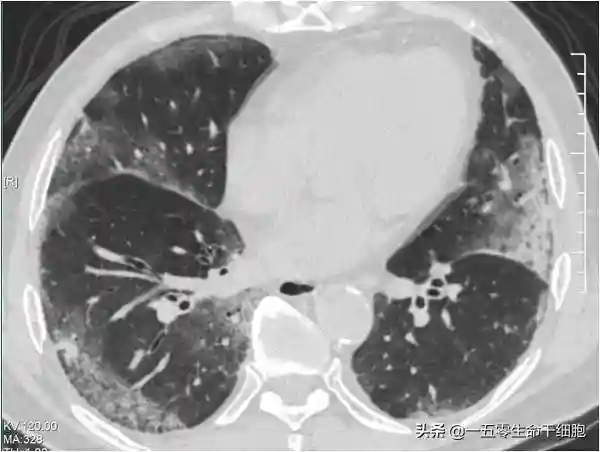

干细胞是一类具有自我更新复制和多向分化潜能的原始细胞群体,已通过小鼠等动物模型和大量临床前研究证实了全身性或气道内输入干细胞对多种肺部疾病(肺损伤、肺纤维化等)有效。

2020年1月27日,浙江省防治新型冠状病毒肺炎专家组成员黄建荣教授受记者采访时透露,发现干细胞对于禽流感患者的肺部感染,肺纤维化有比较好的效果,因此准备对新型冠状病毒重症的病人,应用这样的方法,目前这个项目已通过了医院的伦理委员会的讨论。